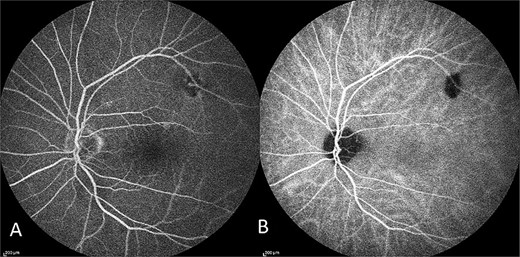

The patient had normal macular FFA and ICG as seen in Fig. 4.

Capture of the patient’s left eye FFA (A) and ICG (B) in midphase. Hypofluorescence along the superior arcade is an area of incidental poor choroidal perfusion.

Secondly, CSCR usually has supporting features for the diagnosis on ICG and FFA which are not demonstrated in this case. The most common signs on FFA at the macular are a pinpoint leak in the early phase, at the mid-phase, the hyper-fluorescence increases in intensity and in the late-phase evolves into a ‘smokestack’ or ‘ink-blot’ pattern [9]. ICG, in CSCR, displays choroidal filing delay in the early phase, hyperpermeability of choroidal vessels with multi-focal hyper-fluorescence around the macular in the mid-phase and fading of this hyper-fluorescence in the late phase [9, 10]. As demonstrated in Fig. 4, the patient had a normal FFA and ICG in mid-phase.